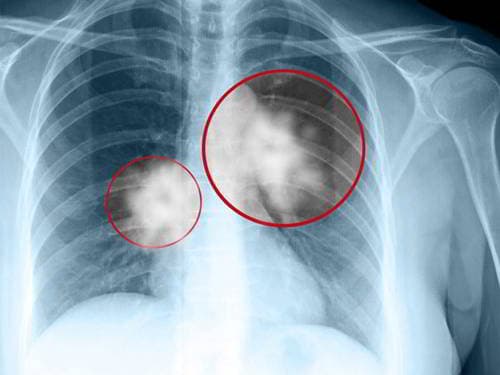

【Cảnh báo】Phổi có vết mờ coi chừng ung thư phổi

Rất nhiều người sau khi thăm khám chụp X quang phổi phát hiện phổi có vết mờ và lo lắng do ung thư phổi. Vậy thực tế, chụp X quang phổi có vết mờ có phải ung thư không? Phổi có vết mờ – chớ coi thường X quang phổi là một trong những xét […]